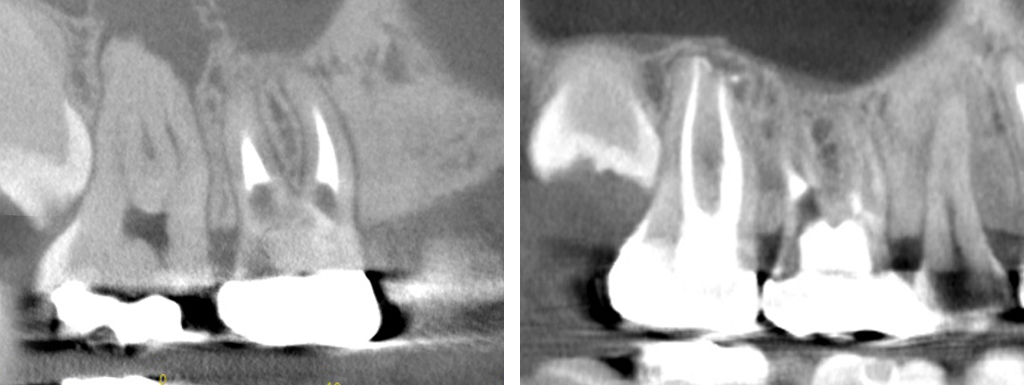

症例9:精密根管治療による治療3